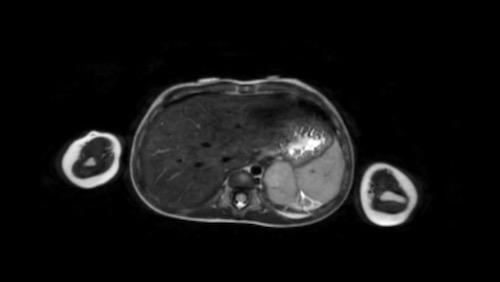

Hình ảnh

Hình ảnh MRI của một bé gái chín tháng tuổi có khối u ở bụng trái. MRI cho thấy khối u tuyến thượng thận trái, một phần đặc, một phần nang. Có nhiều di căn gan.

Khối u đã được sinh thiết. Có tình trạng chảy máu liên tục qua kim dẫn đường. Vào cuối thủ thuật, hai nút bọt gelatin đã được đặt vào (các dải tăng âm (mũi tên)).